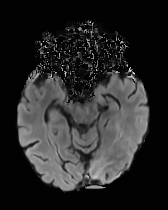

While ACAT revolves around generating counterfactuals, its primary strength lies in accurately identifying pathological regions, which are subsequently employed in a classification pipeline. On the other hand, it falls short in producing credible counterfactual examples, an issue we aim to address in this study. An illustration of this phenomenon is depicted in Figure 2, where we can observe how ACAT is able to generate a saliency map that approximately identifies the pathological region (e, bottom row). However, in the counterfactual example, the lesion remains visible (e, top row). In contrast, our approach not only refines the saliency map but also generates a counterfactual image where the pathology is completely eliminated (f).

In Figures 2 and 4 we display examples of healthy images and anomaly maps obtained with the different approaches. We can observe that f-Ano GAN is not able to generate credible counterfactuals and generally produces images of poor quality and unrealistic appearance. On the other hand, the approaches based on diffusion models are able to create more high-quality results. However, the ones obtained with CG and CFG seem to present some artifacts, which may not only impact the realism of the counterfactual examples but also the precision of the anomaly maps obtained from them. In order to better quantify the capability of these methods to accurately segment pathological areas, we compute the Dice scores of the anomaly maps they generate.